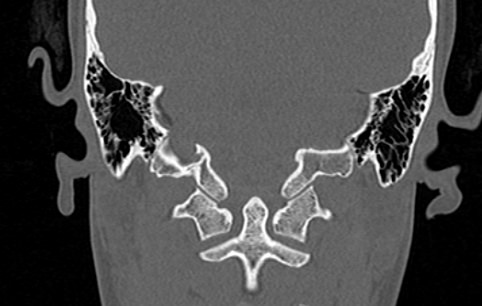

Основание черепа имеет сложное строение. Оно образовано лобными костями, решетчатой и клиновидной костью, височными и затылочными костями. На внутренней поверхности основания черепа лежат структуры ствола мозга, такие как средний мозг, Варолиев мост и продолговатый мозг, переходящий в спинной мозг на уровне большого затылочного отверстия. Поверхность основания черепа имеет многочисленные отверстия, через которые проходят черепно-мозговые нервы и сосуды головного мозга.

Наиболее информативным методом диагностики различных заболеваний в области основания черепа является мультиспиральная компьютерная томография. Исследование проводится с целью оценки травматических повреждений, диагностики аномалий развития костных структур, при планировании оперативных вмешательств, а также выявления воспалительных заболеваний и опухолевых процессов. Также на данном уровне может дифференцироваться аномалия Арнольда-Киари, заключающаяся в эктопии (то есть опущении) миндалин мозжечка различной степени выраженности.

В медицинских центрах «Доступная медицина» установлены новейшие мультиспиральные 64- и 128-срезовый компьютерные томографы экспертного уровня. В результате послойного сканирования с минимальным шагом от 0,5 мм получаются детальные изображения костных структур и прилегающих окружающих тканей. Благодаря инновационным возможностям аппаратов полученные при сканировании данные трансформируются в пространственные модели исследуемой области, которые можно увеличить, повернуть в разные стороны, рассмотреть все структуры в мельчайших подробностях. Новейшее оборудование позволяет проводить точную и достоверную диагностику заболеваний такой труднодоступной области как основание черепа. При этом современные аппараты оказывают минимальное лучевое воздействие на пациента.